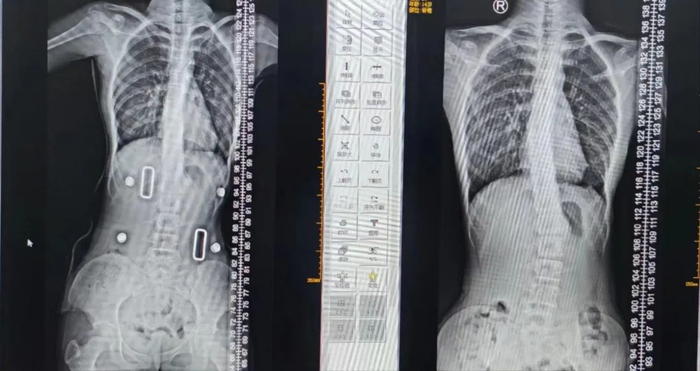

戴支具前

图源/南海人医)

戴支具后